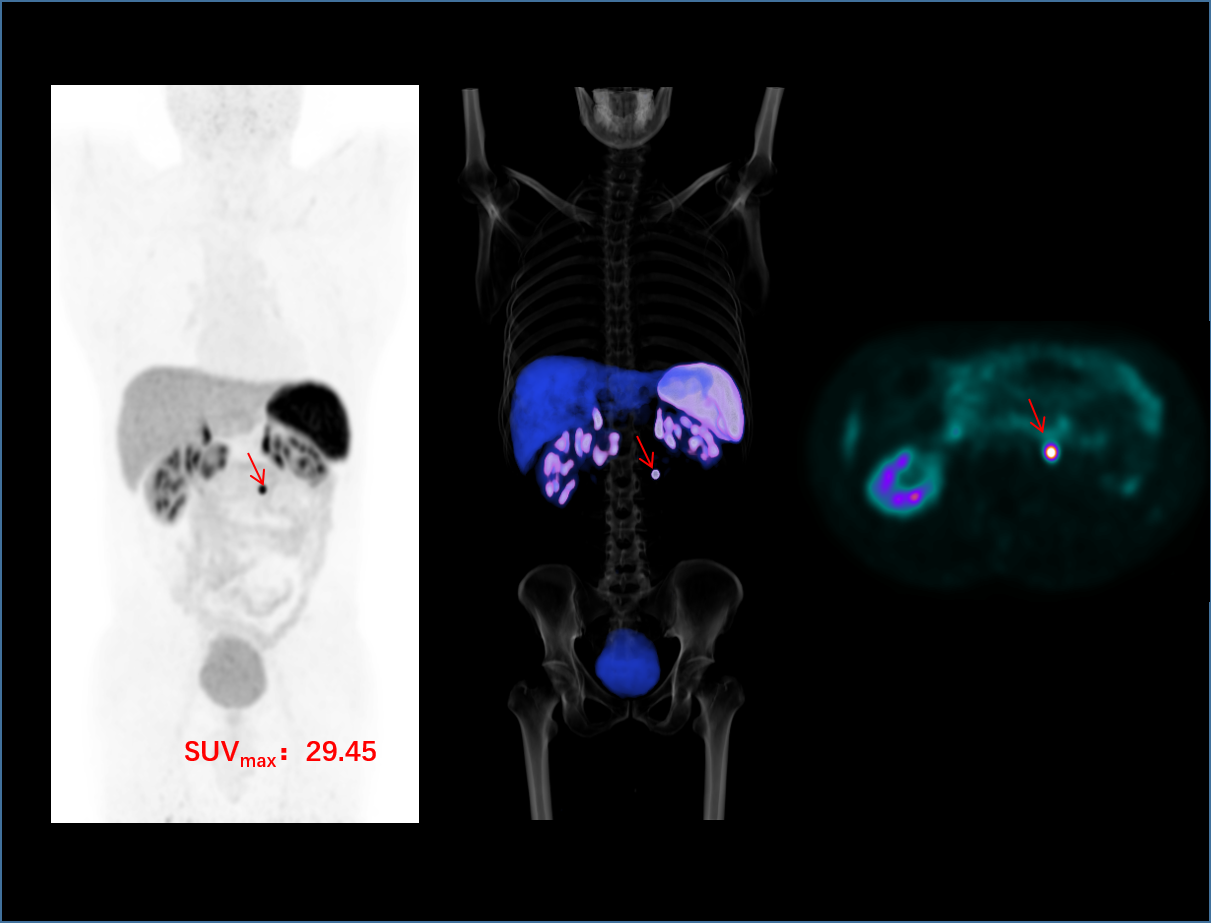

초고 NEMA 해상도

새로운 수준의 혁신적인 분자영상

정밀 영상을 위한 높은 매트릭스 사이즈